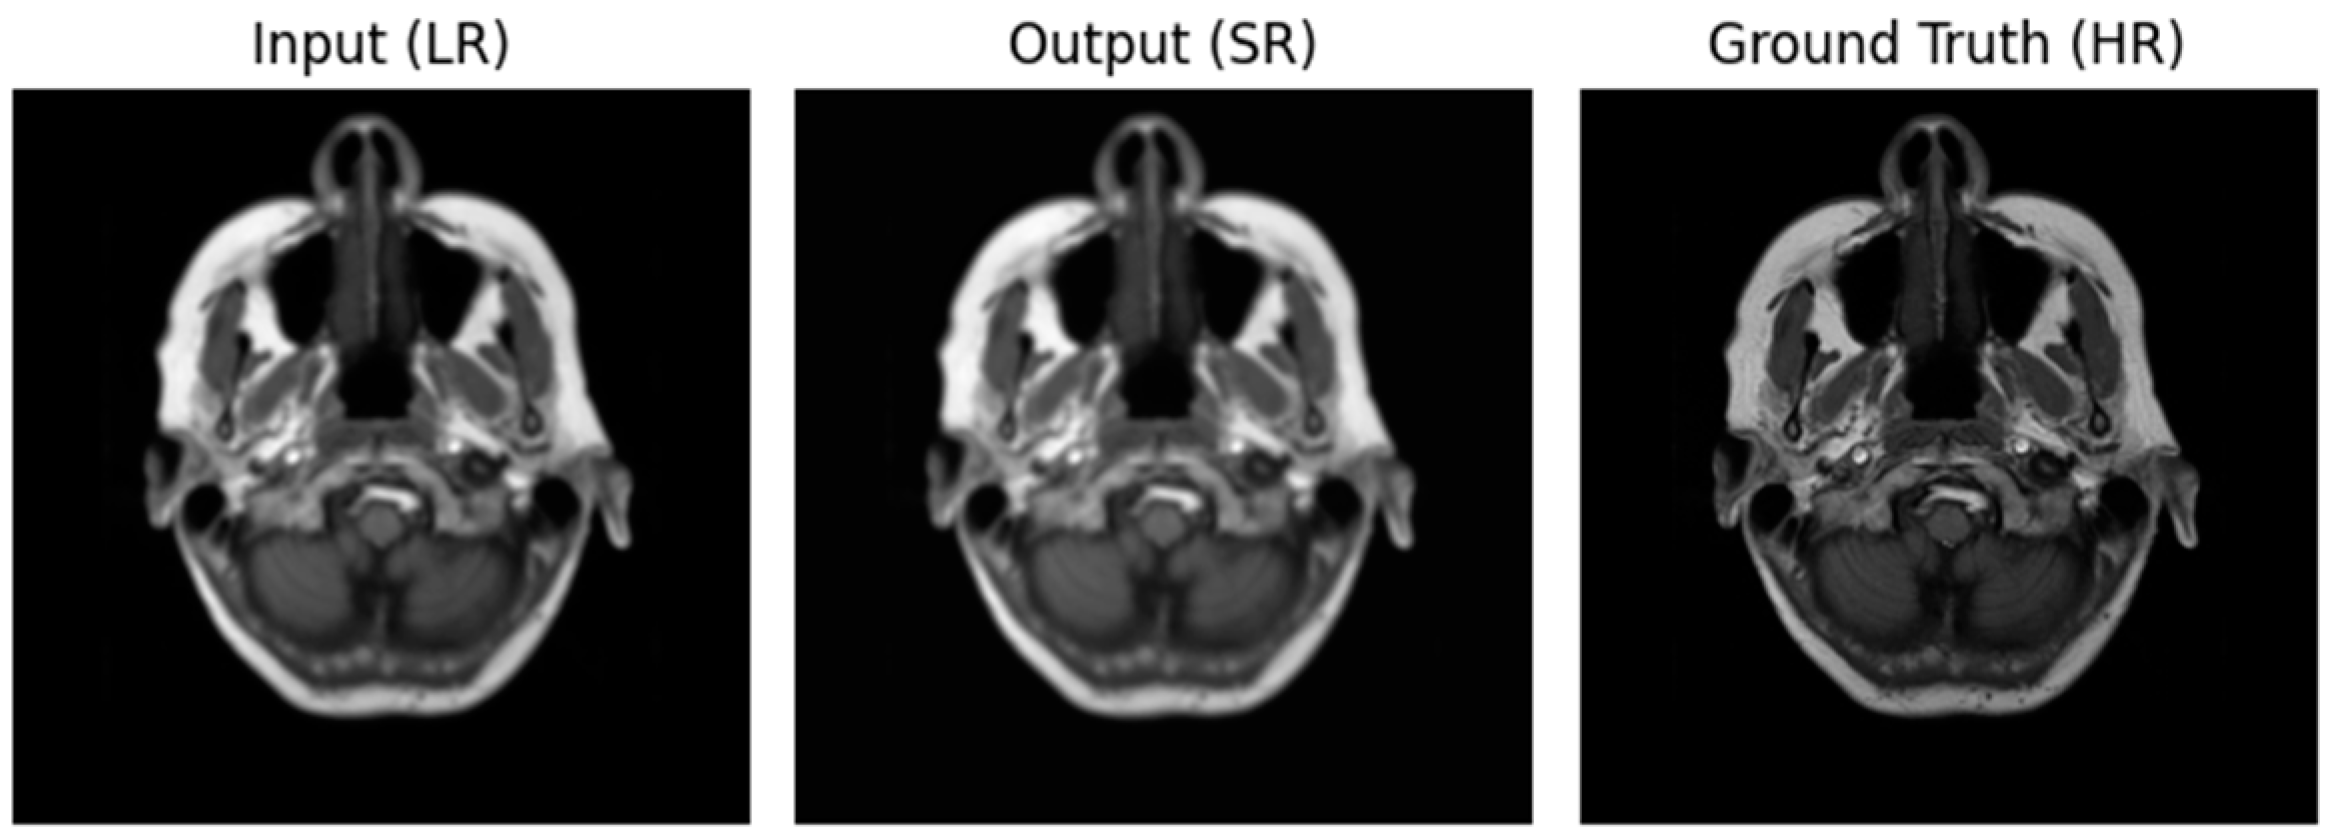

3.2. Performance of ADAM Optimizer and Use of Loss Functions Using Super Resolution Convolution Neural Network (SRCNN)

3.3. Performance of ADAM Optimizer and Use of Loss Functions Using Super Resolution Residual Network (SR ResNet)

3.4. Comparative Analysis Table of SRCNN and SR ResNet with ADAM Optimizer and Loss Functions